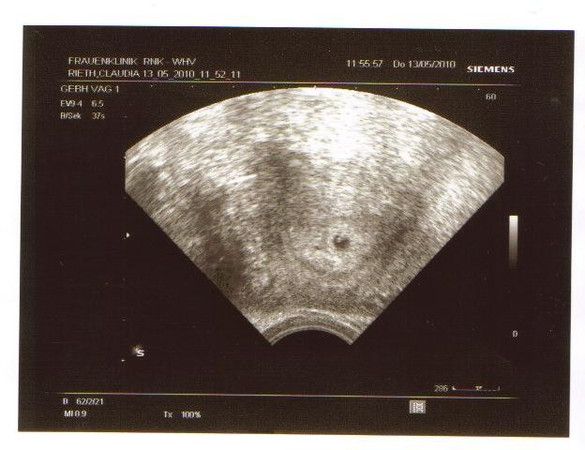

Wir haben es geschaft und ich bin

Schwanger:-)